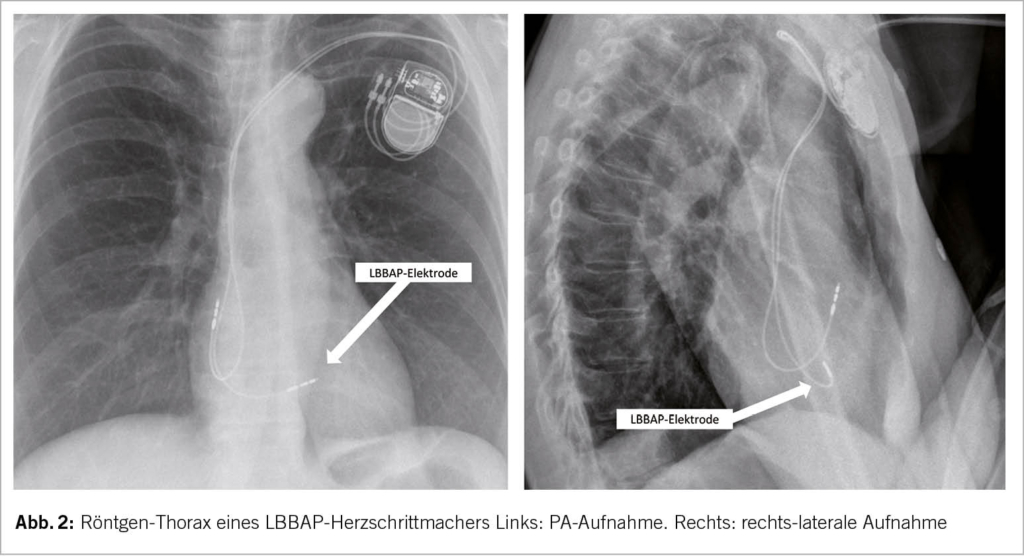

Im Gegensatz zu den HBP-PM zeichnen sich die LBBAP-PM durch stabile Messwerte (Sensing, Impedanzen, Reizschwellen) und weitgehend analoge Device-Programmierung sowie Nachsorge wie die konventionellen RVP-PM aus. Im Alltag fällt bei einer Nachkontrolle eines LBBAP-PM potenziell einzig eine manchmal auf unipolar programmierte Stimulation der LBBAP-Elektrode und auffällig schmale QRS-Komplexe auf, ansonsten unterscheidet sich eine Standardabfrage des LBBAP-PM meistens nicht von einem konventionellen RVP-PM. Auch in der Röntgenkontrolle fällt bis auf eine etwas proximalere Lage der LBBAP-Elektrode kein Unterschied zu einem RVP-PM auf (Abb. 2). Falls in der Nachsorge die LBB-Stimulation erneut geprüft werden möchte, ist diese detaillierte Nachsorge allerdings deutlich umfangreicher: Die LBBAP-Elektrode muss dann unter 12-Kanal-EKG-Ableitungen getestet werden in bipolarer sowie unipolarer Stimulation, sowie in hohem und tiefem Output mit Anwendung der bekannten Kriterien für LBB-Stimulation (Abb. 1, Abb. 3). Bei der LBBAP-Stimulation in bipolarer Konfiguration sollte darauf geachtet werden, ob es gegenüber der unipolaren Stimulation zu rein myokardialer Stimulation mit Verlust der LBB-Stimulation oder auch nur zu einem höheren Anteil an myokardialer Stimulation kommt. Die Wahl des Stimulationsmodus (uni- vs. bipolar) kann anschliessend neben den Reizschwellen auch vom Vorliegen und der Selektivität einer LBB-Stimulation abhängig gemacht werden. Schrittmachersysteme mit LBBAP-Elektroden sind MRI tauglich analog den konventionell implantierten RVP-Elektroden.